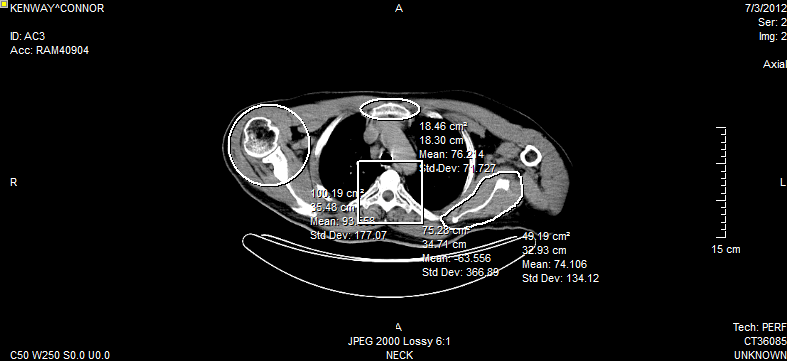

The FreeHand ROI is used by holding down the mouse button and drawing on the image by free hand. Once the mouse button is released, the beginning and ending points of the region are linked by a straight line in order to close off the region. The following image contains one of each of the four possible ROI annotations.

Each annotation display information on the area of the ROI and the Mean and Standard Deviation values of the pixel intensities.